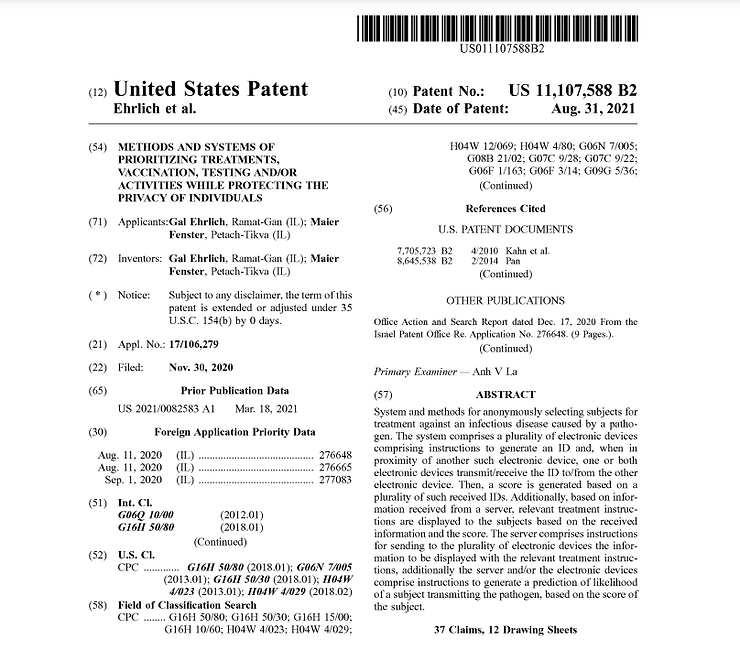

Big Harma’s patent application was approved, August 31st, 2021 and was the very first patent that showed up on a list of over18,500 for the purpose of remote contact tracing of all vaxxinated humans worldwide who will be or are now connected to the “internet of things” by a quantum link of pulsating microwave frequencies at 2.4 gHz or higher from death towers and satellites directly to the graphene ferric oxide held in the fatty and/or connective tissues of all persons inoculated with the Pfizer, Moderna, AstraZenica and J&J COVaids VAXXines.